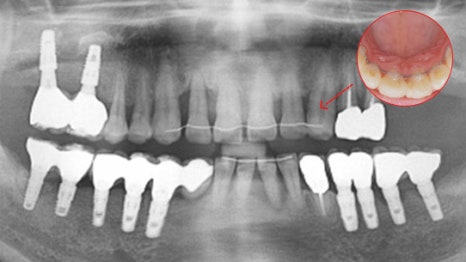

사례 1

과잉진료 없이 꼭 필요한 임플란트만 식립

다른 치과에서 6개 치아 발치 후 12개 임플란트를

권유받았던 환자분이 내원하셨습니다.

연세고운미소치과에서는 레이저 치주 치료를

진행하여 치아를 살리고, 최종적으로 6개의

임플란트만 식립하여 치료를 마무리했습니다.